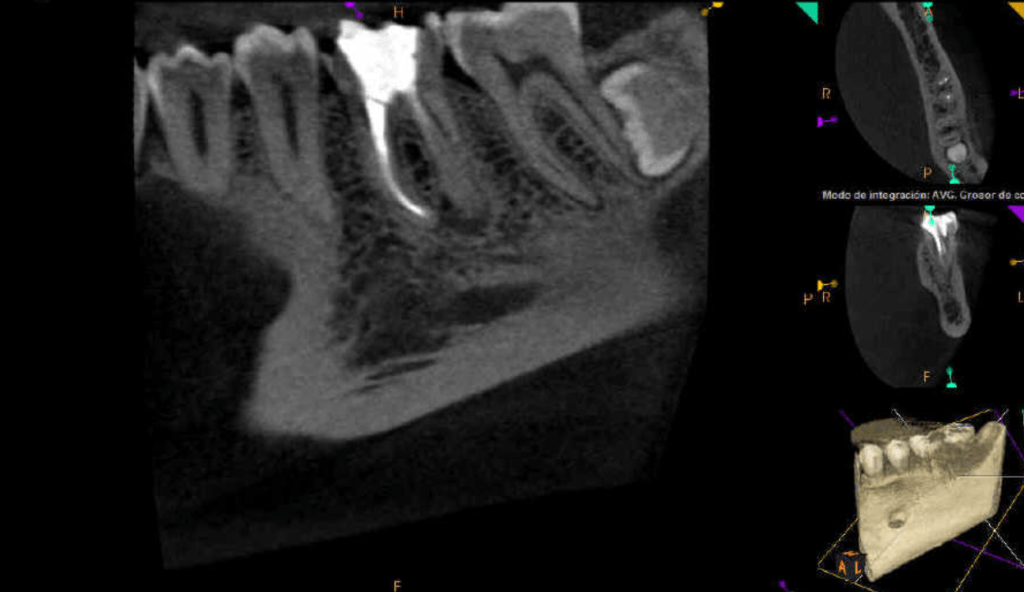

Vertical root fracture